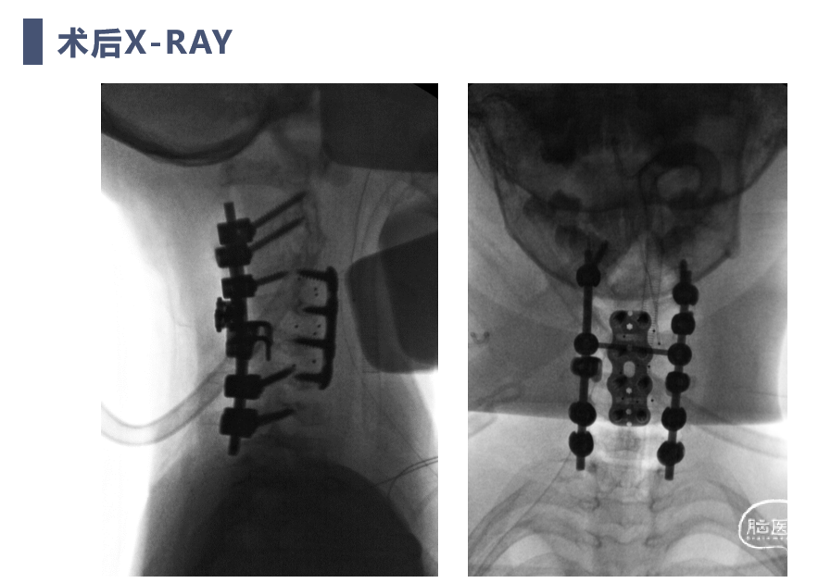

术后X线

双向牵引后,患者后方小关节仍存在一定绞锁,首先行后路手术,充分松解后方绞锁的关节突。再行前路手术,矫正后凸畸形,前路手术时因患者骨量极少,单纯前路螺钉复位力量弱,借助提拉工具完成良好复位。最后翻身行后路手术完成C2-7后路固定,因患者多数侧块发育异常,双侧C4-5无法置钉,应用椎板钩固定,双侧C2椎弓根直径只有3.2mm,但成功置入了两颗3.5mm螺钉。

术后复查患者复位满意,颈痛及神经症状消失,但此类患儿骨性结构发育异常,需要密切随诊,观察有无近端或远端交界性后凸发生。